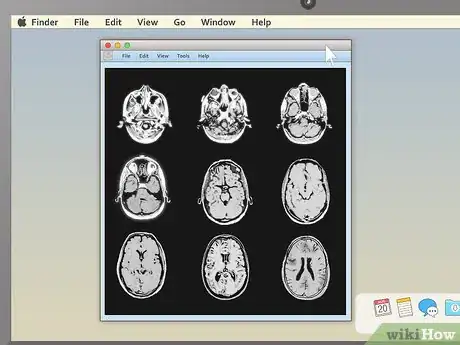

3. 3

Pick an appealing series layout. MRI programs almost always have the ability to display more than one image at once. This makes it convenient for doctors to compare different views of the same area or even MRIs taken at different times. For most non-doctors, it's easiest to simply choose a one-image-at-a-time layout and cycle through the images individually. However, there should be onscreen instructions to show two, four, or many more images at once, so feel free to play around with this feature.

Use cross-sectional views to spot abnormalities in brain MRIs. MRIs of the brain tissue are often used to check for brain tumors, abscesses, and other serious problems that can affect the brain. The easiest way to see these things is usually to choose the cross-sectional view, then descend slowly from the top of the head downward. You're looking for anything that's not symmetrical — a dark or light patch that's on one side but not the other is cause for concern.

• Brain tumors often take the form of round, golf ball-like growths in the brain which will usually show up as either bright white or dull grey surrounded by a ring of white. However, other brain problems (like multiple scleroses) can also have a whitish appearance, so this alone may not be a sign of a brain tumor.